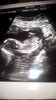

Witam w 19 tygodniu ciąży dowiedziałam się ze będę miała dziewczynkę w 20 tyg okazało się jednak , że to chłopak. Sama już nie wiem bo na jednym usg widać na pewno dziewuche a na drugim chłopca. Może to pempowina ?? Może ktoś mi pomoże rozwiązać ta zagadkę